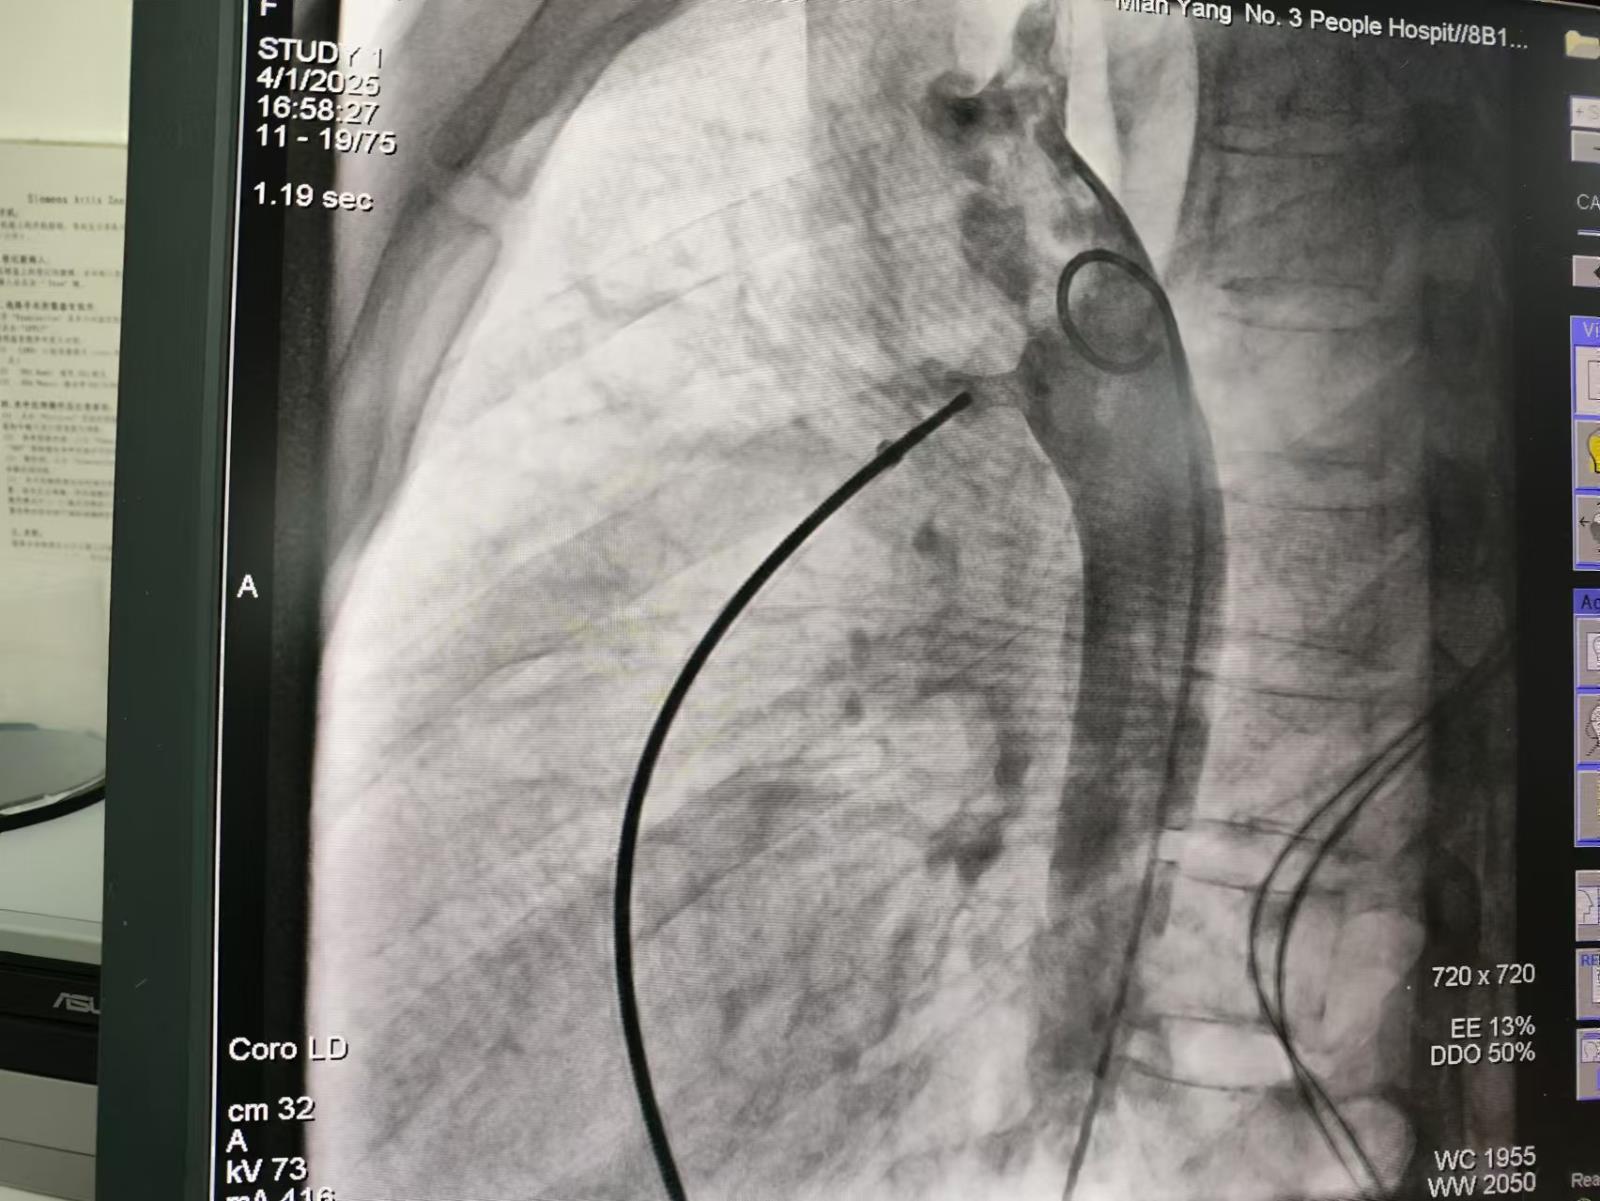

手术医生唐波、沈松林、童健文默契配合,在对患者施行局麻并皮肤消毒后,术中用Seldinger技术,用刀片尖挑开穿刺点处皮肤仅仅约2mm小口,选择合适的含针芯穿刺针对患者双侧的股动脉、股静脉分别进行穿刺,拔出针芯后立即插入导丝并退出穿刺针,通过导丝引入扩张鞘管及猪尾巴造影导管进入主动脉时,快速注入造影剂。X线电影下清晰可见,造影剂从主动脉经未闭的动脉导管向肺动脉分流,形成"喷射征",该患者导管的形态为主动脉端粗、肺动脉端细的漏斗型。

利用介入诊疗中心的大型C臂对动脉导管定量测量:精确测量导管直径及长度、主动脉端至肺动脉端距离,为封堵器尺寸的选择提供科学精准的依据。

医生再在动脉侧送入导丝,静脉侧顺血管通路放入VER建立静脉侧通道,送入抓捕器抓捕主动脉侧通路的导丝,建立主动脉-肺动脉之间的动脉-静脉轨道。顺轨道将VER通过未闭的动脉导管,释放封堵器。封堵后重复造影确认: 封堵器完全覆盖导管开口,无造影剂渗漏,无残余分流。封堵器的腰部完全卡在导管最窄处,盘片紧贴主动脉/肺动脉壁。以确保封堵器的释放成功。肺动脉显影延迟,主动脉弓形态恢复,介入术取得圆满成功。